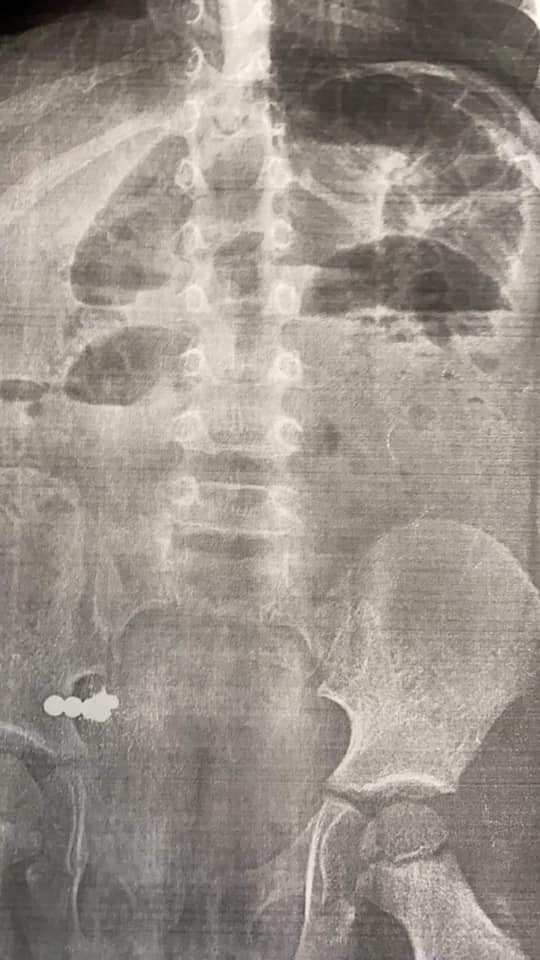

Як повідомили у Львівській обласній дитячій клінічній лікарні ОХМАТДИТ, у дитини болів животик, була рвота і ознаки кишкової непрохідності. Стороннє тіло лікарі побачили на рентгені. Виявилося, що то були магнітики.

Дитині зробили колоноскопію і фіброгастроскопію. Але магнітик вже був у травному тракті, тому його не виявили. Щоб дістати його, довелося провести операцію. За три доби магнітик потрапив зі шлунка у кишківник, викликав кишкову непрохідність, і дістати його інакшим способом просто було неможливо.